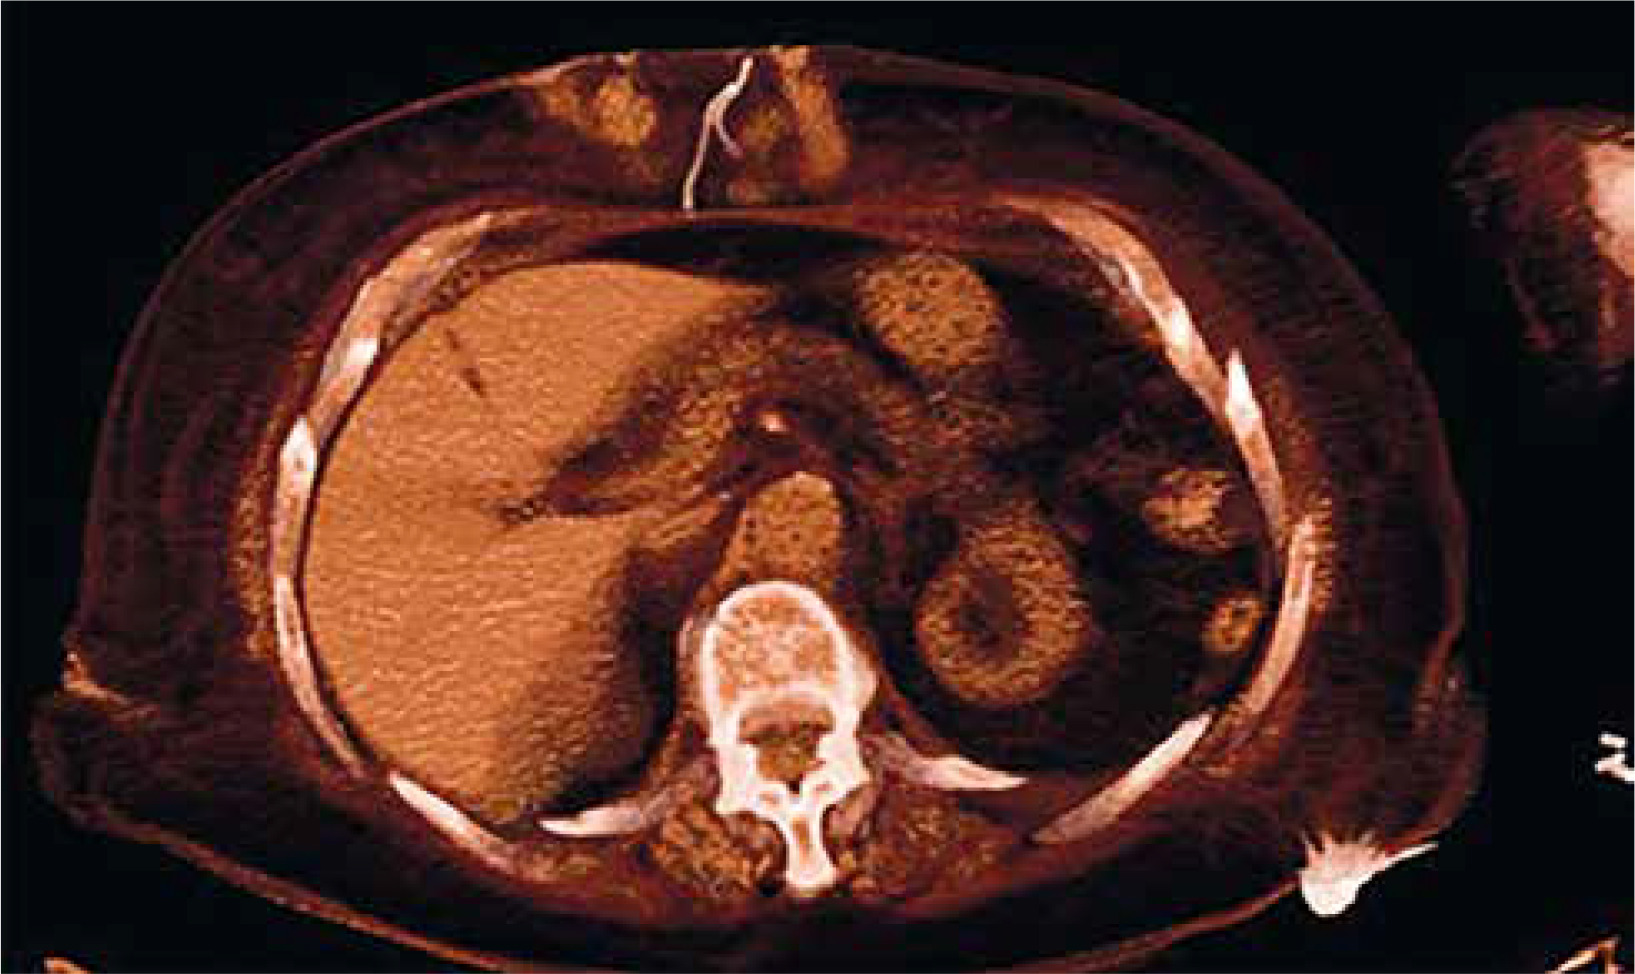

The patient did not develop fever but her blood count showed the normal range of hemoglobin, 11 g/dl, increase of white blood cell count, 12,500 per µl, and C-reactive protein level of 70 g/l. As the swelling kept draining and growing despite antibiotic therapy and serial medication, the patient was hospitalized once again in January 2019 to remove the granuloma surgically. During the post-operative follow-up the wound initially presented with a superficial dehiscence that eventually reached the deep edges of the wound; therefore a computed tomography (CT) scan was performed and it revealed the presence of a foreign body in the patient’s mediastinum which appeared to be the retained TEPWs (Figures 2–4).

Figure 2

Computed tomography (CT) scan images of the retained wires in the subcutaneous tissues of the patient (axial plane)